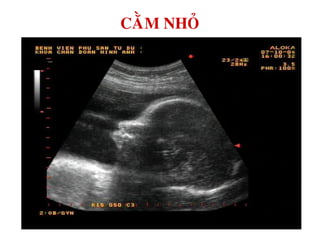

CAÈM NHOÛ